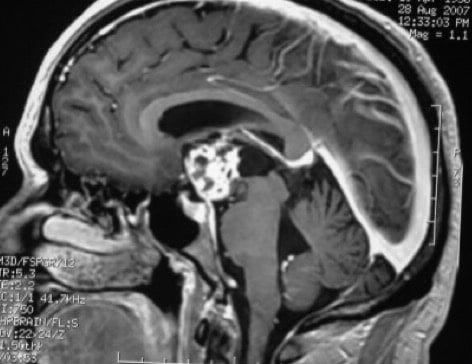

Adenoma secretante

Por lo menos la mitad de todos los prolactinomas son muy pequeños (menos de 1 centímetro o 3/8 de una pulgada de diámetro). Estos pequeños tumores ocurren con más frecuencia en las mujeres y son llamados microprolactinomas.

Los tumores más grandes son más comunes en los hombres. Tienden a ocurrir a una edad avanzada. El tumor puede crecer hasta un tamaño grande antes de que aparezcan los síntomas. Los tumores más grandes de 3/8 pulgadas (1cm) de diámetro son llamados macroprolactinomas.